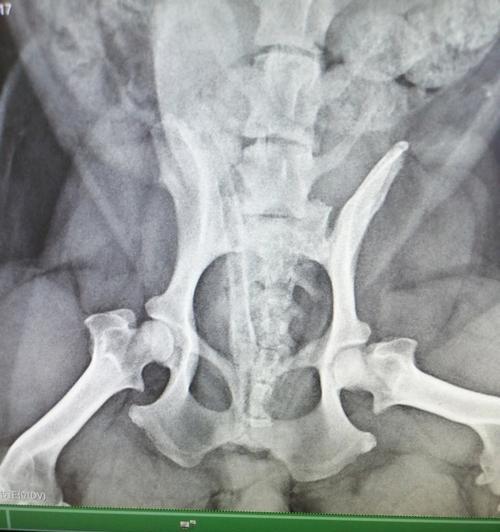

狗狗腿髋坏死(了解腿髋坏死的原因与治疗方法,为宠物狗的健康尽一份责任) 狗狗腿髋坏死会严重影响它的行动与生活质量。了解血液供应不足等病因,把握早期症状,从非手术理疗到高级手术,选择合适的治疗方案并做好术后康复与心理关怀,才能真正帮助爱犬减轻痛苦,重回健康生活。 宠物 2026-03-28 08:15 浏览:715